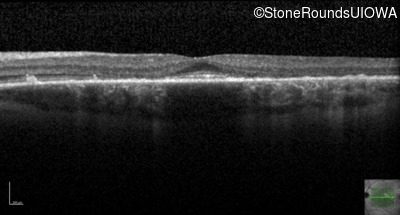

Age at visit: 30 years

This 30 year old man first noticed poor vision in dim light when he was five years old. His visual acuity began to fall in his early 20's.